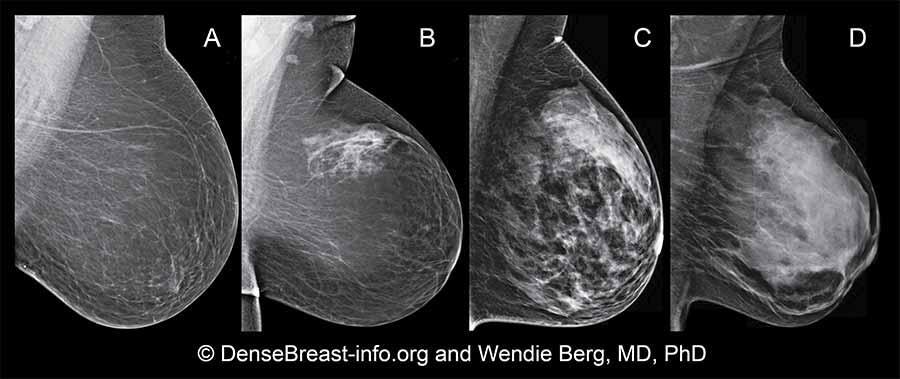

Iowa Army of Pink: Bạn dày đặc đến mức nào?

Viết bởi: Brigid Greening Bạn dày đặc đến mức nào? Đó là một câu hỏi rất quan trọng mà mọi phụ nữ cần có khả năng trả lời liên quan đến mô vú của mình. Câu chuyện của tôi:Vào ngày...